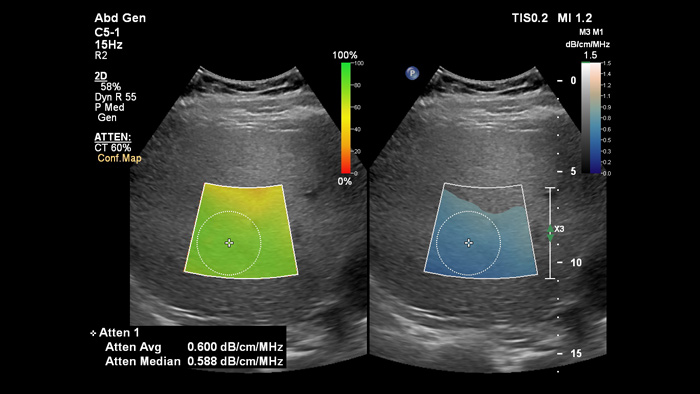

L'imagerie d'atténuation permet de mesurer la quantité de graisse présente dans le foie en calculant le coefficient d'atténuation du son absorbé par le parenchyme hépatique. Cette méthode fournit des paramètres d'atténuation quantitatifs qui peuvent vous aider à gérer les patients atteints de stéatose hépatique.

Imagerie d'atténuation